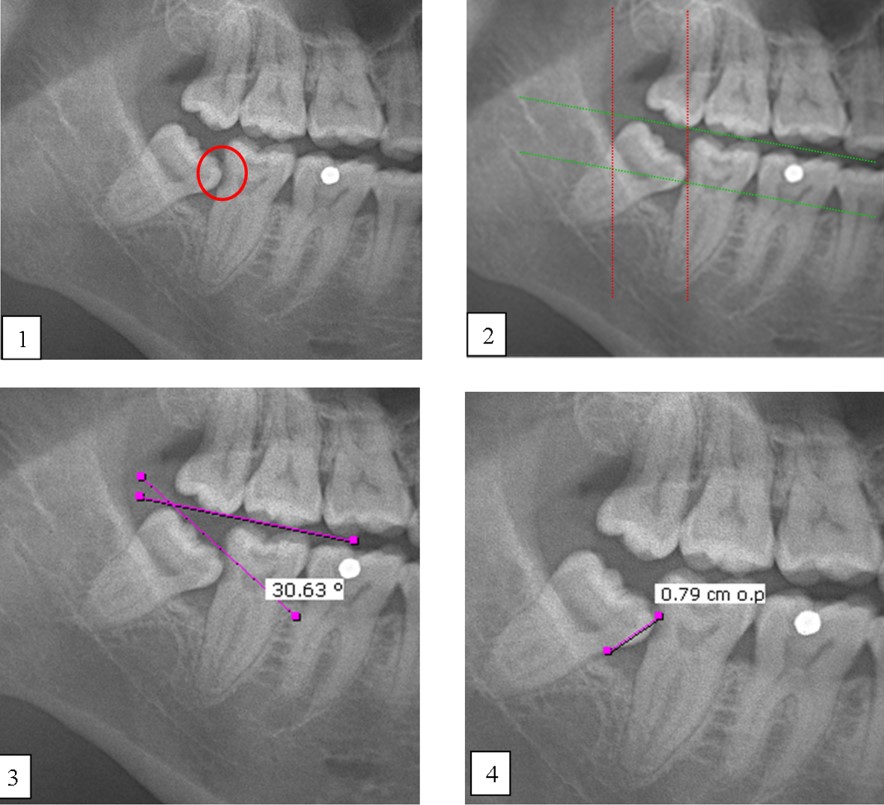

Caries and impacted MTM impaction: (1) Distal caries on MSM; (2) The depth and space of MTM was determined by the Pell & Gregory classification method; (3) The Shiller classification applied in determining the angulation of impacted third molar; (4) The distance between the distal CEJ of the MSM and mesial CEJ of the MTM was calculated as described in Leone classification